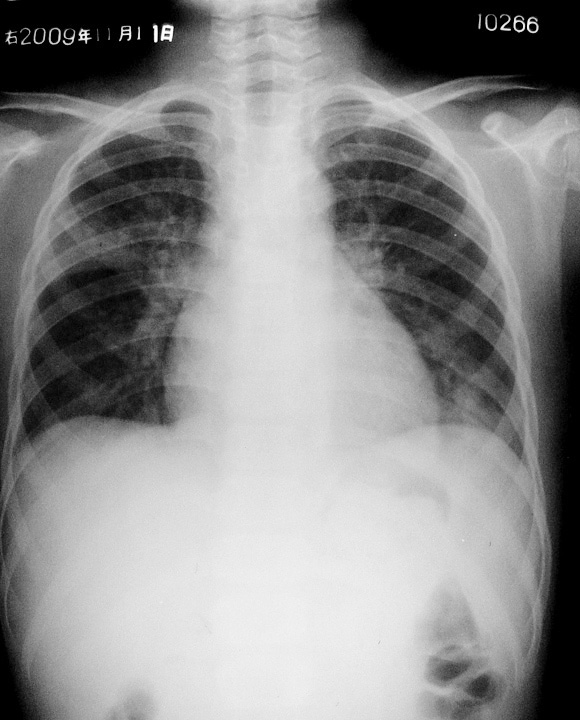

男,12岁,面部及双下肢浮肿5天,临床诊断为急性肾炎。

右肺上叶,左肺尖,左肺近心膈角处可见斑片状阴影,密度不均,边缘不清。考虑双肺感染,建议治疗后复查

谢谢大家,此例病人问题主要是在右上肺第三、四肋间的片状阴影。左下肺炎性感染灶是有的,右水平裂上片状阴影,不小心会误诊为结核,结合临床,患都并无结核症状,而肾炎最常见的并发症为肺部感染。综合一下,首先考虑炎性感染,抗炎治疗后复查。

发病前不少患者有呼吸道感染,以后有反复咯血,大多数出现在肾脏病变之前,长者数年(最长可达12年),短者数月,少数则在肾炎后发生。x线检查见两肺有弥漫性或结节状阴影,自肺门向周围扩散,肺尖及近膈肌处清晰,常一侧较重,有的无咯血史,但经痰含铁血黄素及胸片检查证实有出血。在咯血时肺弥散功能减退,出现低氧血症,贫血常见。

以上是肺——肾病综合征的表现。综合分析吧